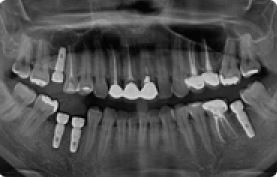

| 8 |

|

임플란트 상악동거상술 전후사례 | 2020.03.06 |